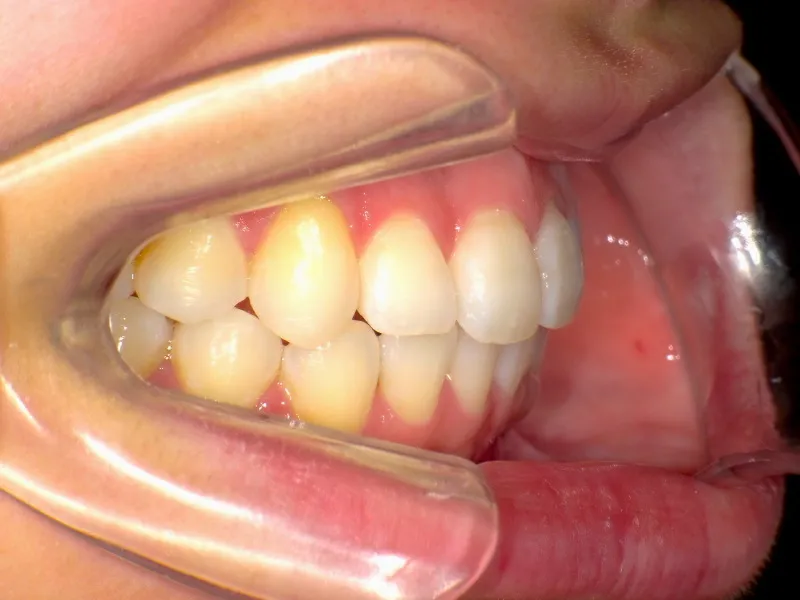

治療終了後

上下ガタガタで、下の歯は癒合歯(2本がくっついて1本の歯)です。

治療前と治療後で下の歯の銀歯がなくなっています。

これは銀歯の第1大臼歯を抜いて第2大臼歯、第3大臼歯の親知らずを使いました。

コルチコトミーという矯正法で歯根への負担を軽減しながら治療しました。

治療回数71回、3年5ヶ月の治療期間で矯正治療を終了しました。

主訴が改善され、ご満足頂きました。